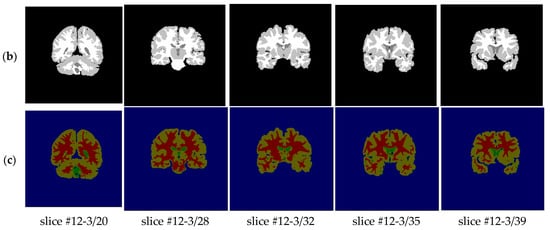

With regard to the T1-weighted MRI brain datasets, the performance of the HMRF-WOA was evaluated for 20 normal subjects. Figure 18 shows some slices of one subject (slices 20, 28, 32, 35, and 39); Figure 18a presents the initial slices images, (b) represents the ground truth segmentation, and (c) shows the HMRF-WOA segmentation results.

Moreover, Figure 18 illustrates the segmentation results of the proposed algorithm using MR brain images from the IBSR database. Figure 18a presents the slices of the original brain image; Figure 18b is the ground truth slice images; and Figure 18c shows the segmented brain MR images using the HMRF-WOA approach on the sample image of one subject. GM is shown in yellow, WM in red, CSF in green, and the background in blue.

Figure 18. Segmentation results of IBSR dataset: (a)—initial images; (b)—ground truth images; (c)—segmentation results.